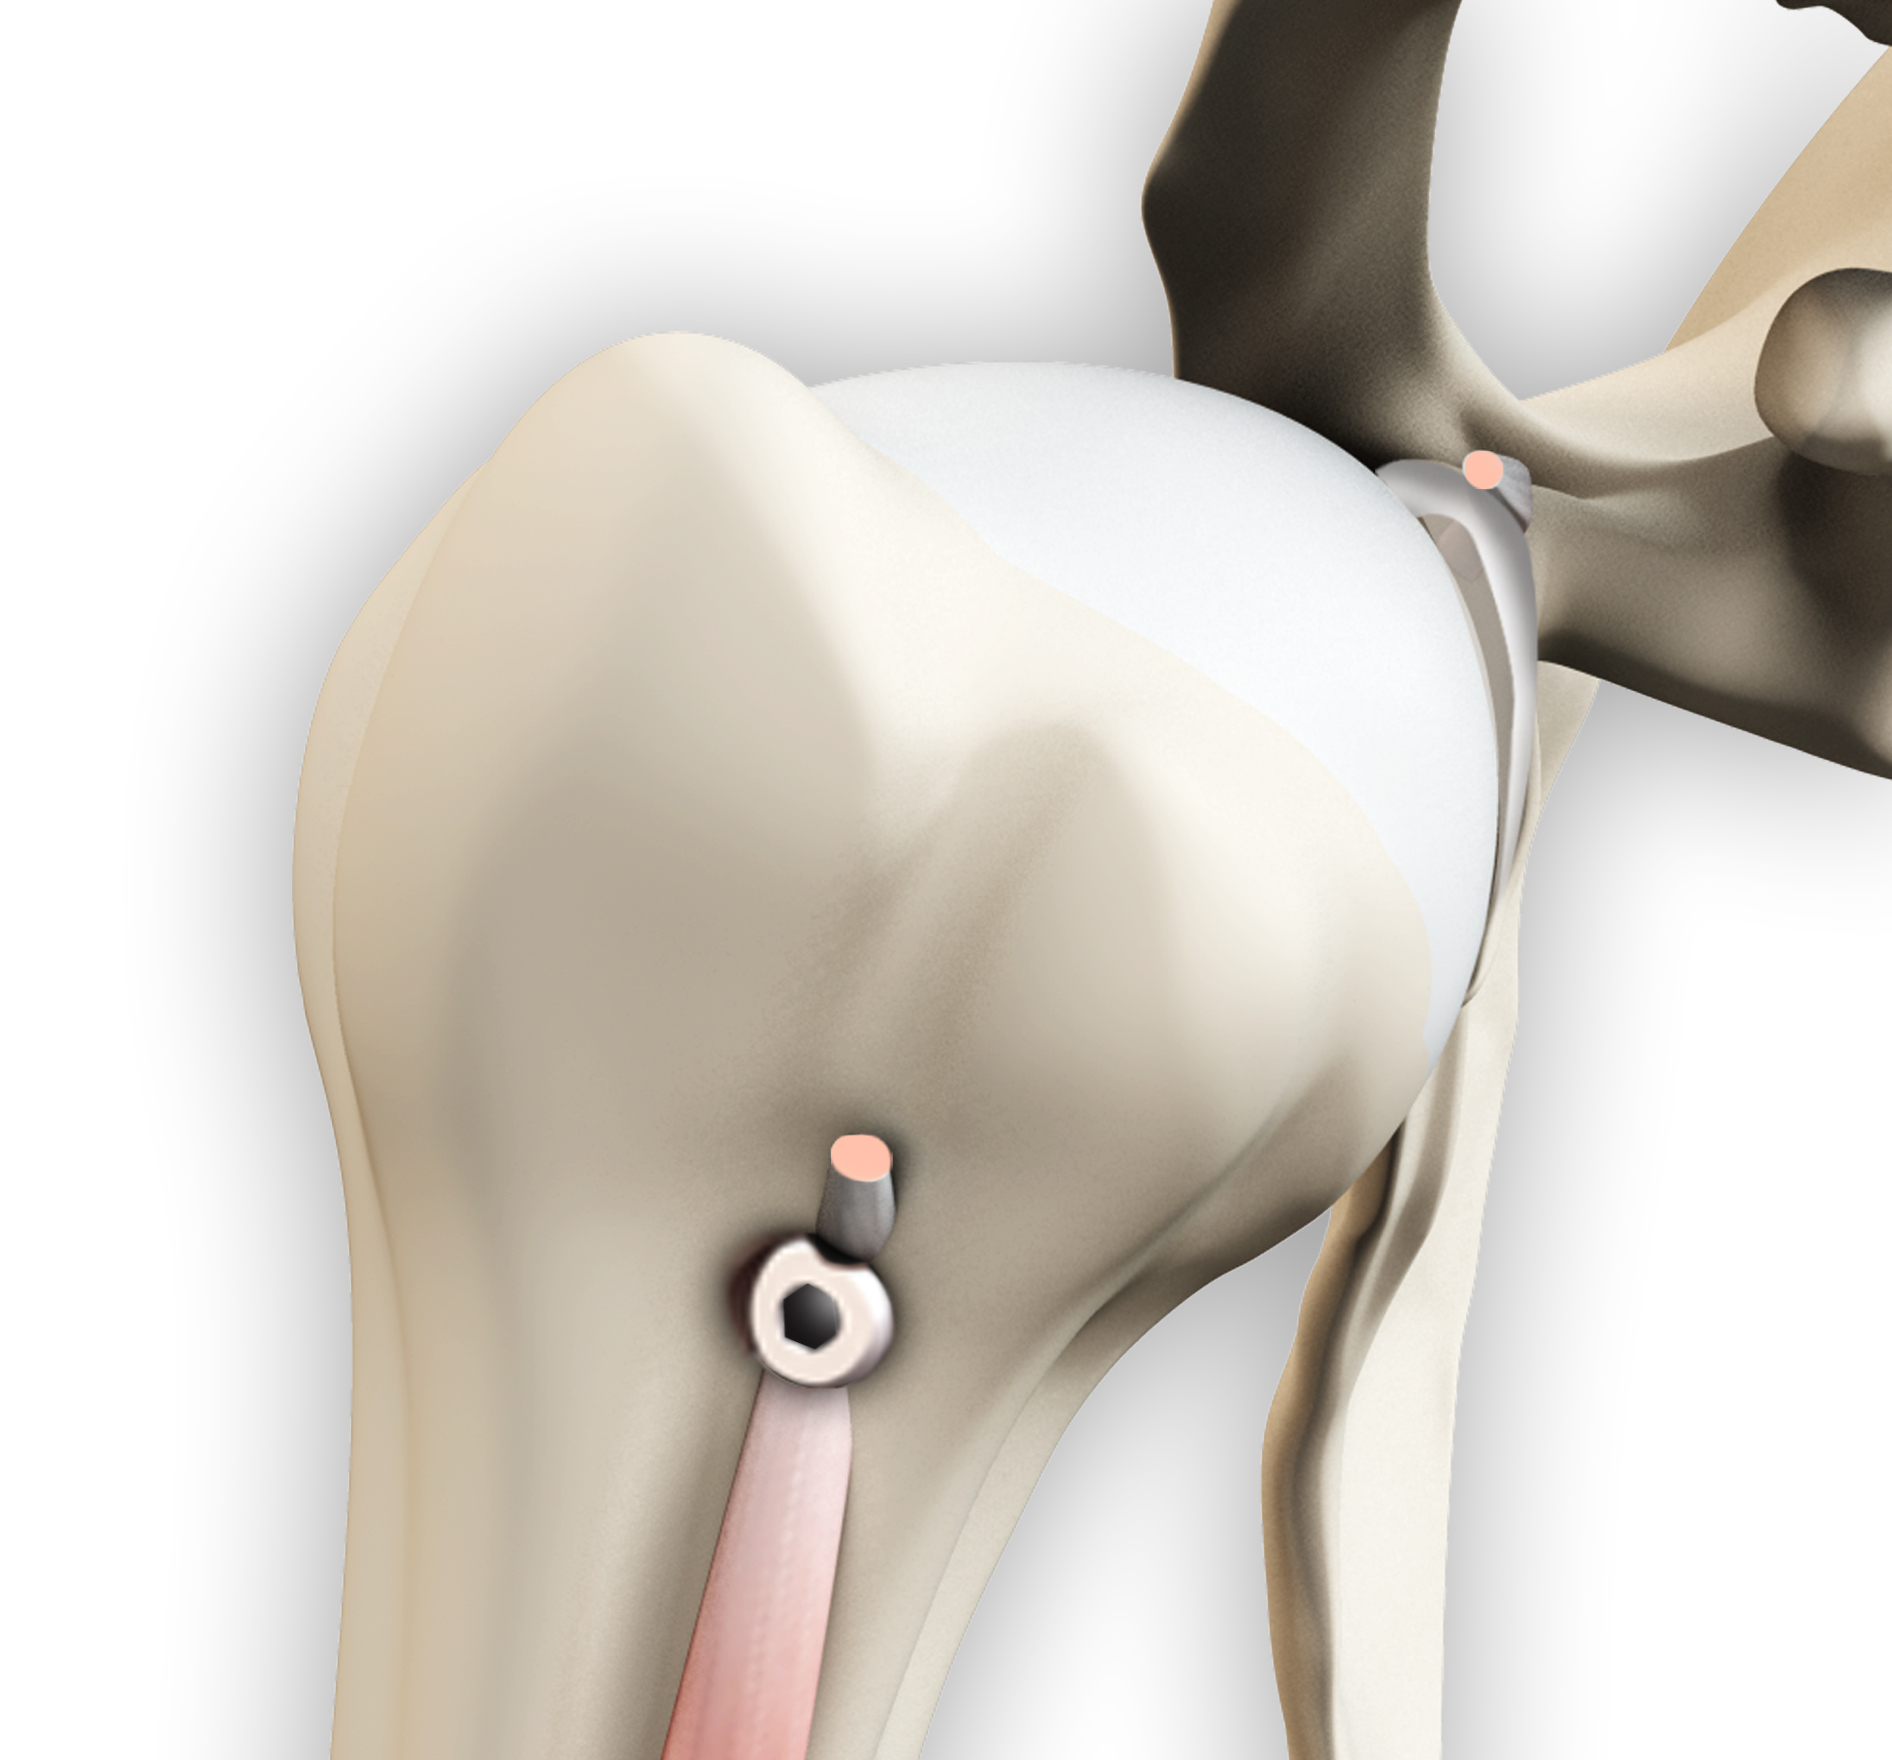

Proximal Biceps Tenodesis

Proximal biceps tenodesis is the surgical reattachment of a torn proximal biceps tendon, which connects the upper part of your biceps muscle to the shoulder.